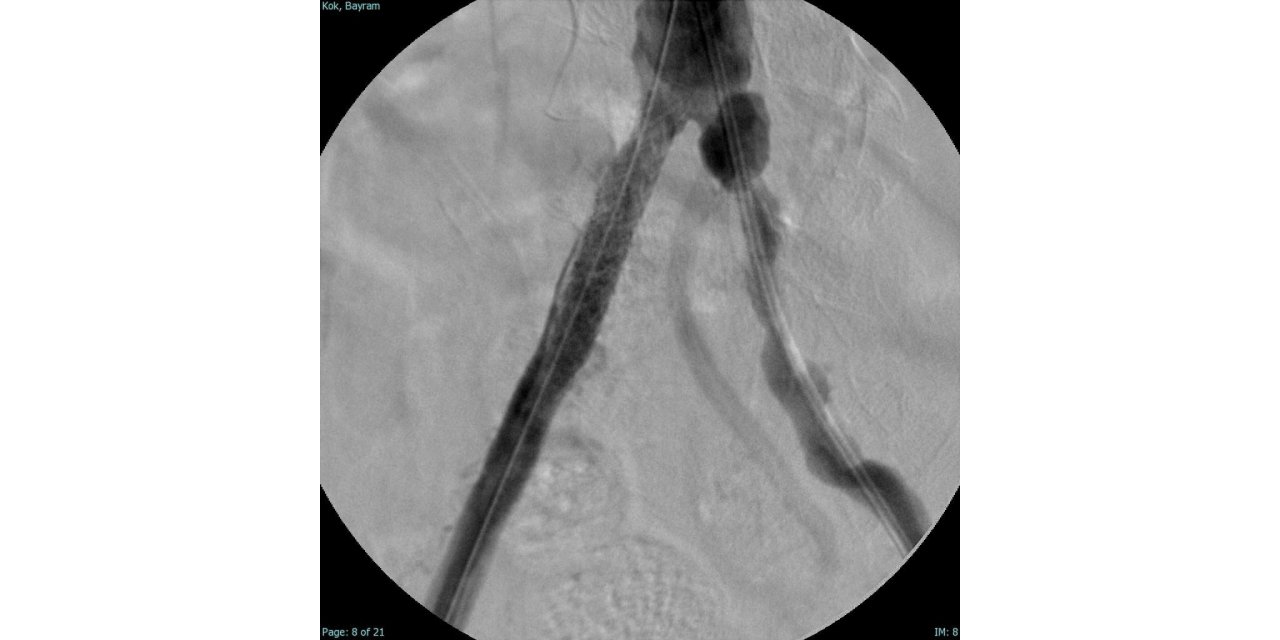

Damar tıkanıklığına INVAMED’ten yapar damar çözümü